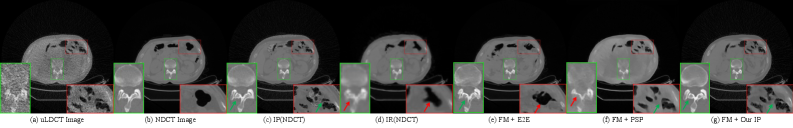

Figure 1: Motivation for the Image Purification (IP) strategy. (a) Ultra-low-dose CT (uLDCT) image with severe noise affecting structural clarity. (b) Corresponding normal-dose CT (NDCT) image for (a). Zoomed-in black areas show anatomical structure morphology. (c) NDCT image after IP processing, used as the label during training. (d) NDCT image after image registration. (e) Denoising result of end-to-end trained Flow Matching (FM) [15] on (a). (f) Denoising result of Flow Matching [15] trained with the PSP[14] strategy on (a). (g) Denoising result of our Flow Matching [15] trained with the IP strategy on (a). Red arrows in (c)-(g) indicate inconsistent structures; green arrows indicate consistent structures.

Fig.1(a) shows a uLDCT image with extreme noise, severely compromising the clarity of anatomical structures. Fig.1(b) is the corresponding normal-dose CT (NDCT) image, serving as the "ground truth" reference. Comparing the zoomed-in regions (black areas) of (a) and (b) reveals clear differences in anatomical structure morphology. Directly training a network with such misaligned data pairs causes the model to learn incorrect mappings, leading to anatomical distortion in the denoised results—i.e., failing to preserve the original tissue structure of the input uLDCT image. This structural distortion can directly impact diagnostic accuracy and is a major obstacle to the clinical application of uLDCT denoising technology.

To address this spatial misalignment, researchers have explored various methods.[16] Image registration is a classical approach in medical imaging for resolving spatial misalignment, including traditional methods like rigid [17], affine [18], and non-rigid deformable registration [19]. Recently, deep learning-based methods have surpassed traditional ones in both accuracy and speed, such as VoxelMorph [20] and uniGradICON [21]. However, for the large deformations caused by respiration and extreme noise interference between uLDCT and NDCT, these registration algorithms perform poorly and struggle to achieve precise alignment. As shown in Fig.1(d), even using the advanced uniGradICON [21] for registration, the result still shows deficiencies in overall resolution (green box) and anatomical registration accuracy (red box). Recent work attempted to mitigate misalignment by filtering out misaligned image patches via data cleaning. However, on extremely noisy uLDCT data, this method filters out too much data, leading to under-training. As shown in Fig.1(f), the flow matching model [15] trained with the PSP[14] strategy produces denoised results with severe structural blurring and loss of detail.

Fig.1(e) and Fig.1(g) further compare the denoising effects under different strategies. Fig.1(e) shows the denoising result of applying an end-to-end trained flow matching model [15] to (a). The red arrows indicate regions where the structure is inconsistent with the original uLDCT, showing the model’s failure to preserve the original anatomical contours. In contrast, Fig.1(g) shows the denoising result of flow matching [15] trained with our proposed IP strategy. The green arrows indicate regions where the structure is consistent with the original uLDCT, demonstrating the exceptional ability of the IP strategy to maintain anatomical integrity. Fig.1(c) shows the NDCT image after processing by the IP strategy, which serves as a structurally aligned label during training and is key to achieving high-quality denoising.